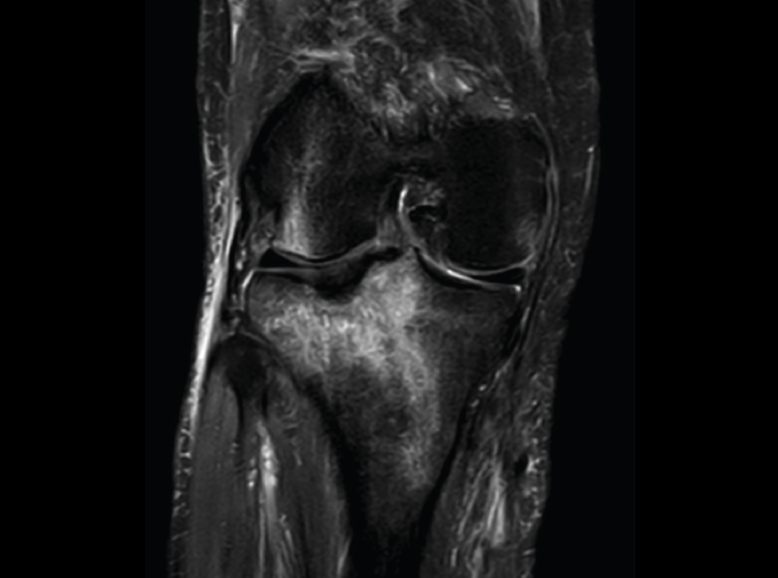

2. Fracturas

Se observa una hiposeñal de la médula ósea en secuencias T1 e hiperseñal en STIR o saturación grasa T2.

2.1. Edema óseo y fractura subcondral (Figura 47)

Figura 47. Corte de secuencia coronal T2 Fat-Sat de RM de rodilla: zona de edema óseo en la meseta tibial externa por contusión.

2.2. Fractura reciente (Figura 48)

Figura 48. Corte de secuencia coronal T2 Fat-Sat de resonancia magnética de rodilla: edema de médula ósea en la meseta tibial externa que ayuda al diagnóstico de fractura reciente en caso de duda.

2.3. Fractura de estrés (Figura 49)

Figura 49. Corte de secuencia sagital T1 de RM de rodilla: imagen lineal en el cóndilo femoral externo por fractura de estrés.